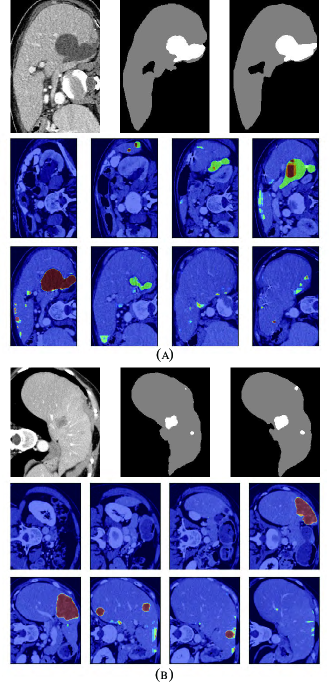

Refer to caption

Figure 9: Tumor segmentation results based on RA-UNet-\@slowromancapii@. (a) is from the LiTS validation dataset, and (b) is from the 3DIRCADb dataset. From left to right, the first row of each subplots indicates the raw images, segmentation results of liver tumor, and the corresponding ground truth. The second and the third rows show the probability heat map of tumor segmentation results.

Tumors were tiny structures compared to livers. Therefore, no interpolation or resizing was applied on tumor patch sampling to avoid information loss from image scaling. It was difficult to decide what size of patch for training could reach a desirable performance. In order to determine the patch size, we set the patch size of 32×\times32×\times32, 64×\times64×\times32, and 128×\times128×\times32 respectively to test the performance of tumor segmentation. Results showed that 128×\times128×\times32 patch-sized data achieved a best tumor segmentation performance. The larger the patch size was, the richer context in formation the patches could provide. While due to the limitation of computational resource, 128×\times128×\times32 was chosen empirically for tumor patches. We randomly picked 150 patches from each liver volume in the boundary box. Totally, 17,700 patches were chosen from LiTS as training and validation datasets. As shown in Table V, our method reached 0.595 and 0.830 Dice scores on the LiTS test dataset and the 3DIRCADb dataset respectively. Fig. 9 shows the tumor segmentation results in details.